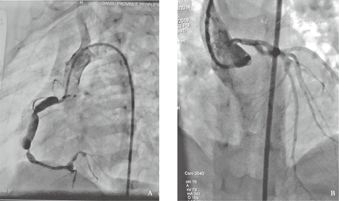

依据ECHO测量结果及患儿体表面积计算出相应的Z值,其中最小Z值为-2.0(对应的冠状动脉内径为1.5 mm,属正常);最大为5.73(对应的冠状动脉内径为6 mm)。选择本组研究中Z值=5.73,即Z值最大的患儿,行选择性CAG,结果提示巨大冠状动脉瘤形成。具体描述为:RCA全程扩张,中段内径6 mm,中远段8 mm,呈瘤样扩张;LMCA内径3.5 mm,LAD呈"串珠样"改变,最宽处4.7 mm。CAG检查提示RCA连续囊状扩张,最宽处8 mm(大于ECHO测量内径),内未见血栓,有侧支循环形成,中远段中度扩张,并有数个瘤体形成;LMCA及左前降支明显增宽,局部数个瘤体形成,见图1。

A.选择性右冠状动脉造影:右冠状动脉连续囊状扩张,呈"串珠样"改变,侧支循环形成,中远段中度扩张,并有数个瘤体形成;B.选择性左冠状动脉造影:左冠状动脉主干及左前降支明显增宽,局部数个瘤体形成。